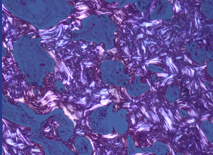

Inflammation of joints

* Marker = rheumatoid factor, auto ab against Fc IgG

* Histo = lots of lymphocytes + plasma cells in synovial tissue

* Acute phase = inflammatory granulaion tissue (pannus) + hyperplastic synovium

* Chronic phase = fibrosis, deformity